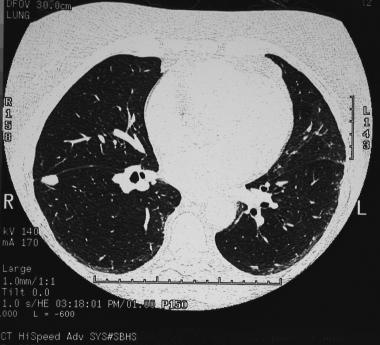

Очаговые образования в легких на КТ выявляются лучше, чем на обзорной рентгенографии. На КТ можно различить очаговые изменения размером 3–4 мм, также лучше визуализируются специфические морфологические признаки (характерные, например, для округлого ателектаза или артерио-венозной мальформации). Кроме того, КТ позволяет лучше оценить те области, которые обычно плохо различимы на рентгенограммах: верхушки легких, прикорневые зоны, а также реберно-диафргамальные синусы. Также на КТ может быть обнаружен множественный характер очагового поражения; КТ может применяться для стадирования опухоли; помимо этого, под контролем КТ осуществляется игольная биопсия.

Субплевральные очаги в легких — что это? Компьютерная томография демонстрирует узловое образование, прилежащее к междолевой плевре. Признаки подобных очагов не являются специфичными и требуют дополнительного обследования. Биопсия подтвердила грибковую инфекцию.